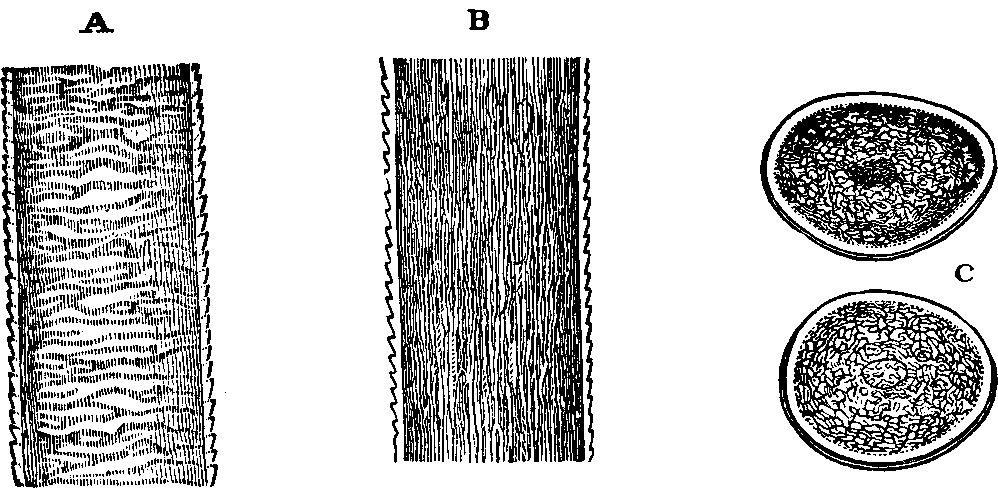

Fig. 38. Red corpuscles of human blood, represented at

a, as they are seen when rather beyond the focus of the

microscope; and at b as they appear when, within the focus.

Magnified 400 diameters.

Fig. 39.

Development of human lymph and chyle-corpuscles into red corpuscles of

blood. A. A lymph, or white blood-corpuscle. B. The same in

process of conversion into a red corpuscle. C. A lymph-corpuscle

with the cell-wall raised up around it by the action of water. D. A

lymph-corpuscle, from which the granules have almost disappeared. E.

A lymph-corpuscle, acquiring color; a single granule, like a nucleus,

remains. F. A red corpuscle fully developed.

Blood is the animal fluid by which the tissues of the body are

nourished. This pre-eminently vital fluid permeates every organ,

distributes nutritive material to every texture, is essentially modified by

respiration, and, finally, is the source of every secretion and excretion.

Blood has four constituents: Fibrin, Albumen, Salts (which elements, in

solution, form the liquor sanguinis), and the Corpuscles.

Microscopical examination shows that the corpuscles are of two kinds, known

as the red and the white, the former being by far the more

abundant. They are circular in form and have a smooth exterior, and are on

an average 1/3200 part of an inch in diameter, and are about one-fourth of

that in thickness. Hence more than ten millions of them may lie on a space

an inch square. If spread out in thin layers and subjected to transmitted

light, they present a slightly yellowish color, but when crowded together

and viewed by refracted light, exhibit a deep red color. These

blood-corpuscles have been termed discs, and are not, as some have

supposed, solid material, but are very nearly fluid. The red corpuscles